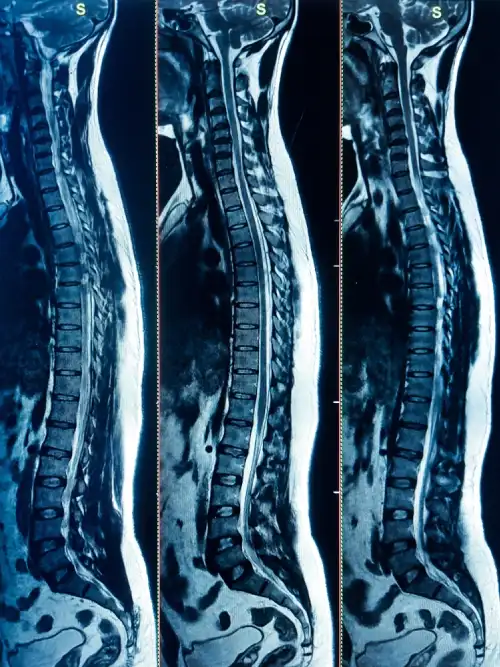

T2 Fracture Pre Op

T7 Pre Op fracture